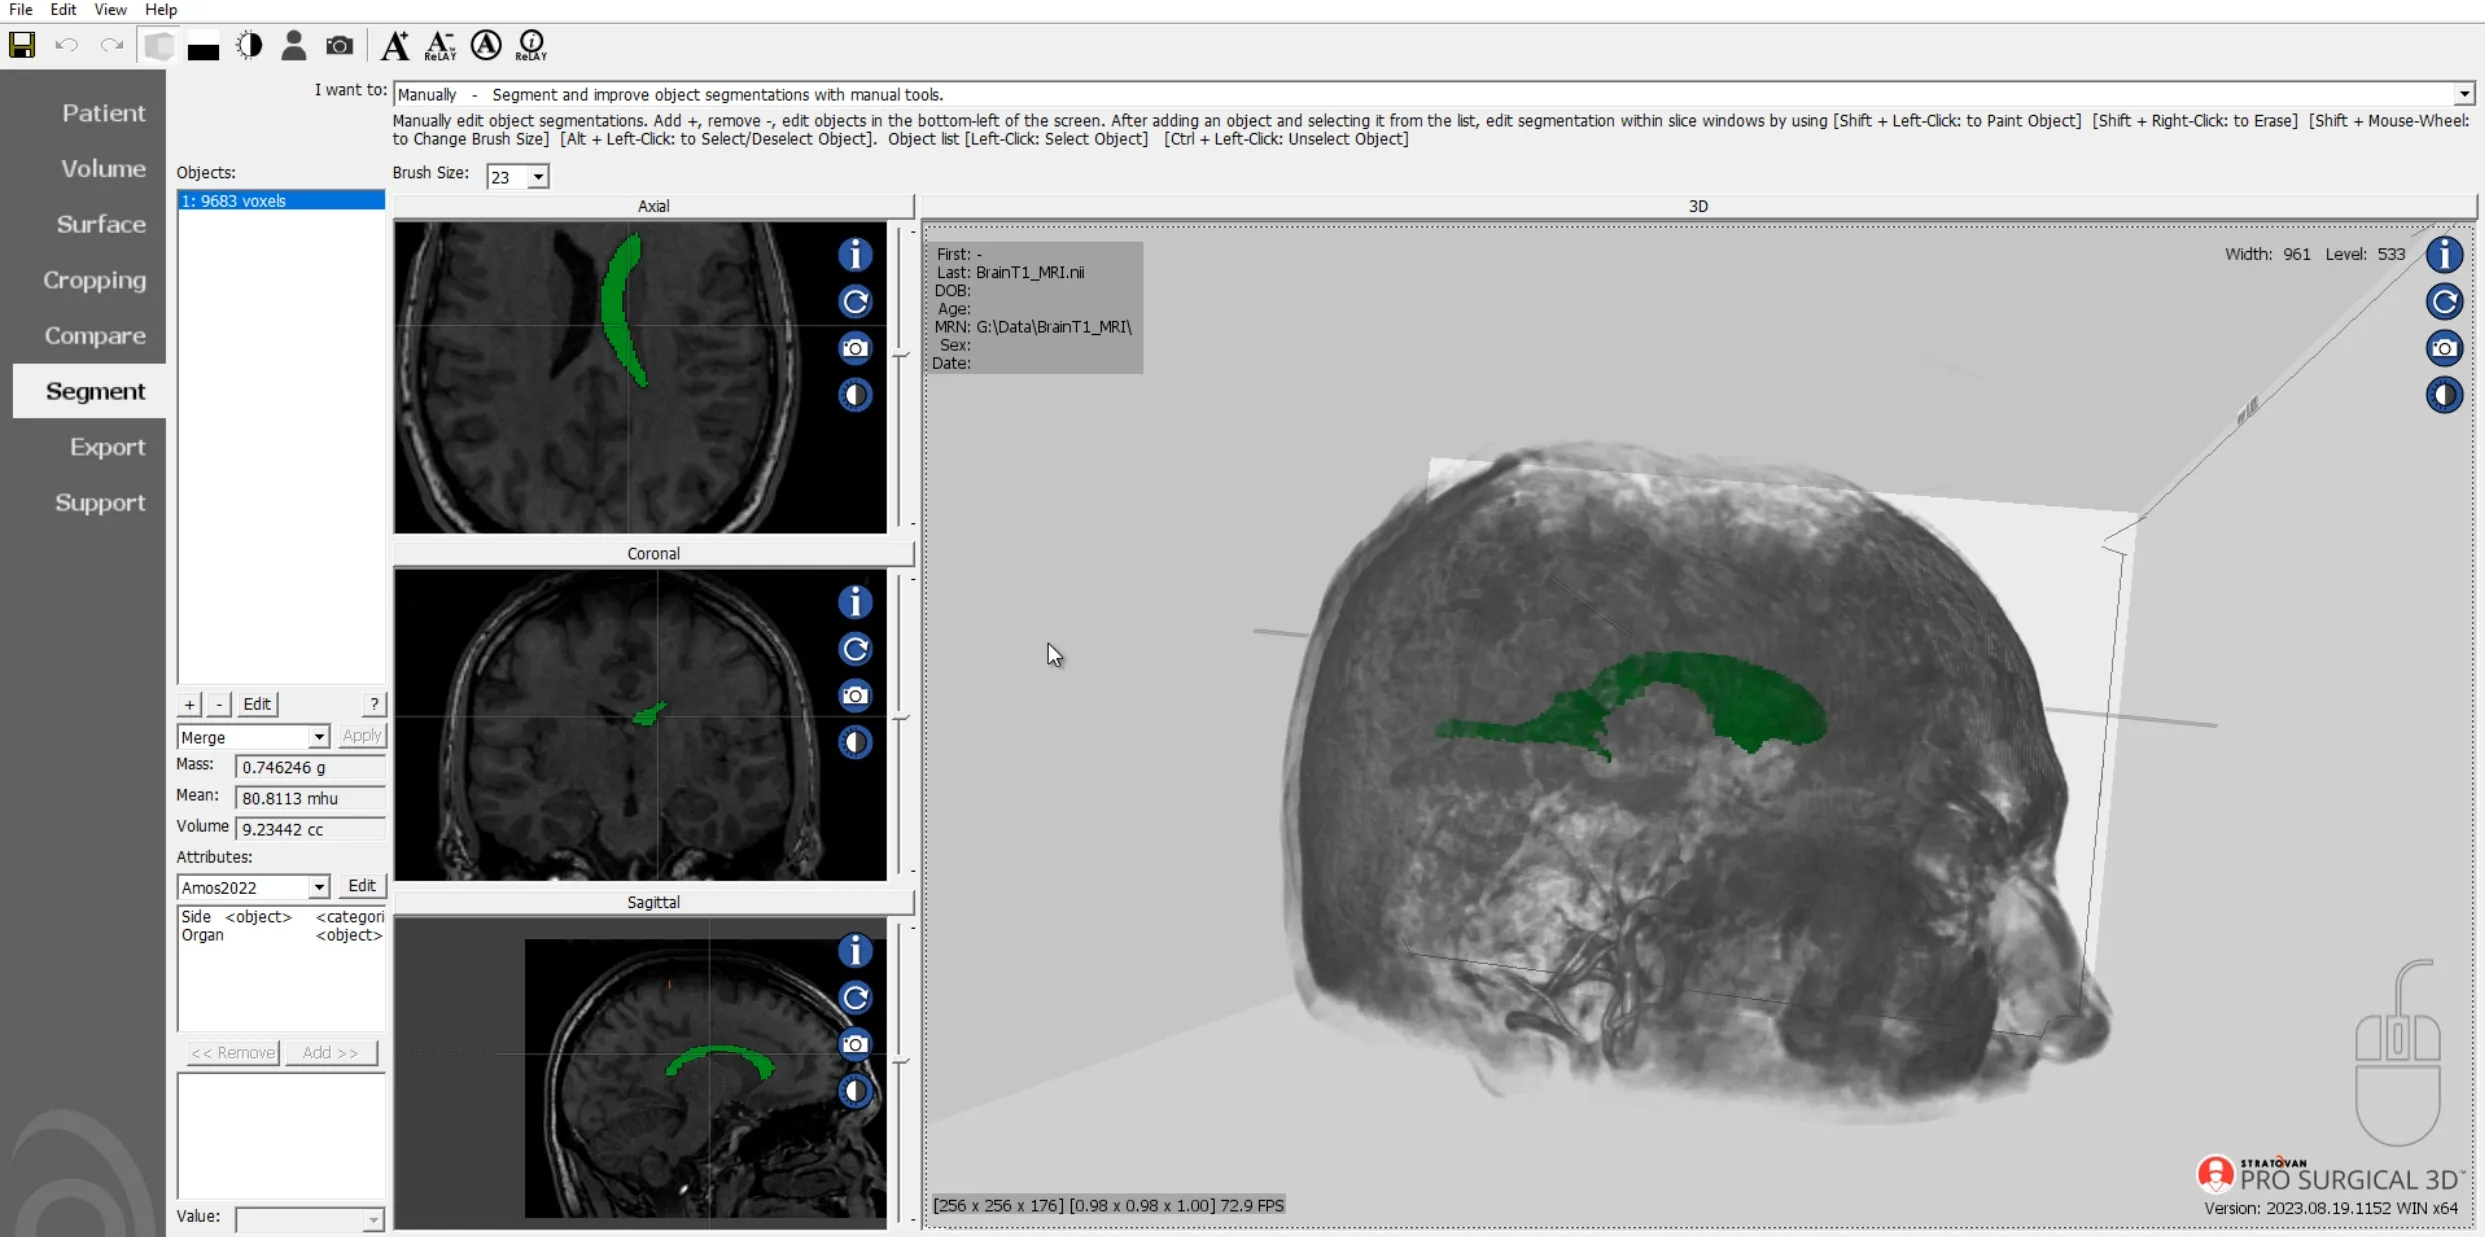

MRI segmentation of human brain ventricle

Quality assurance review of the AMOS 2022 Grand Challenge data